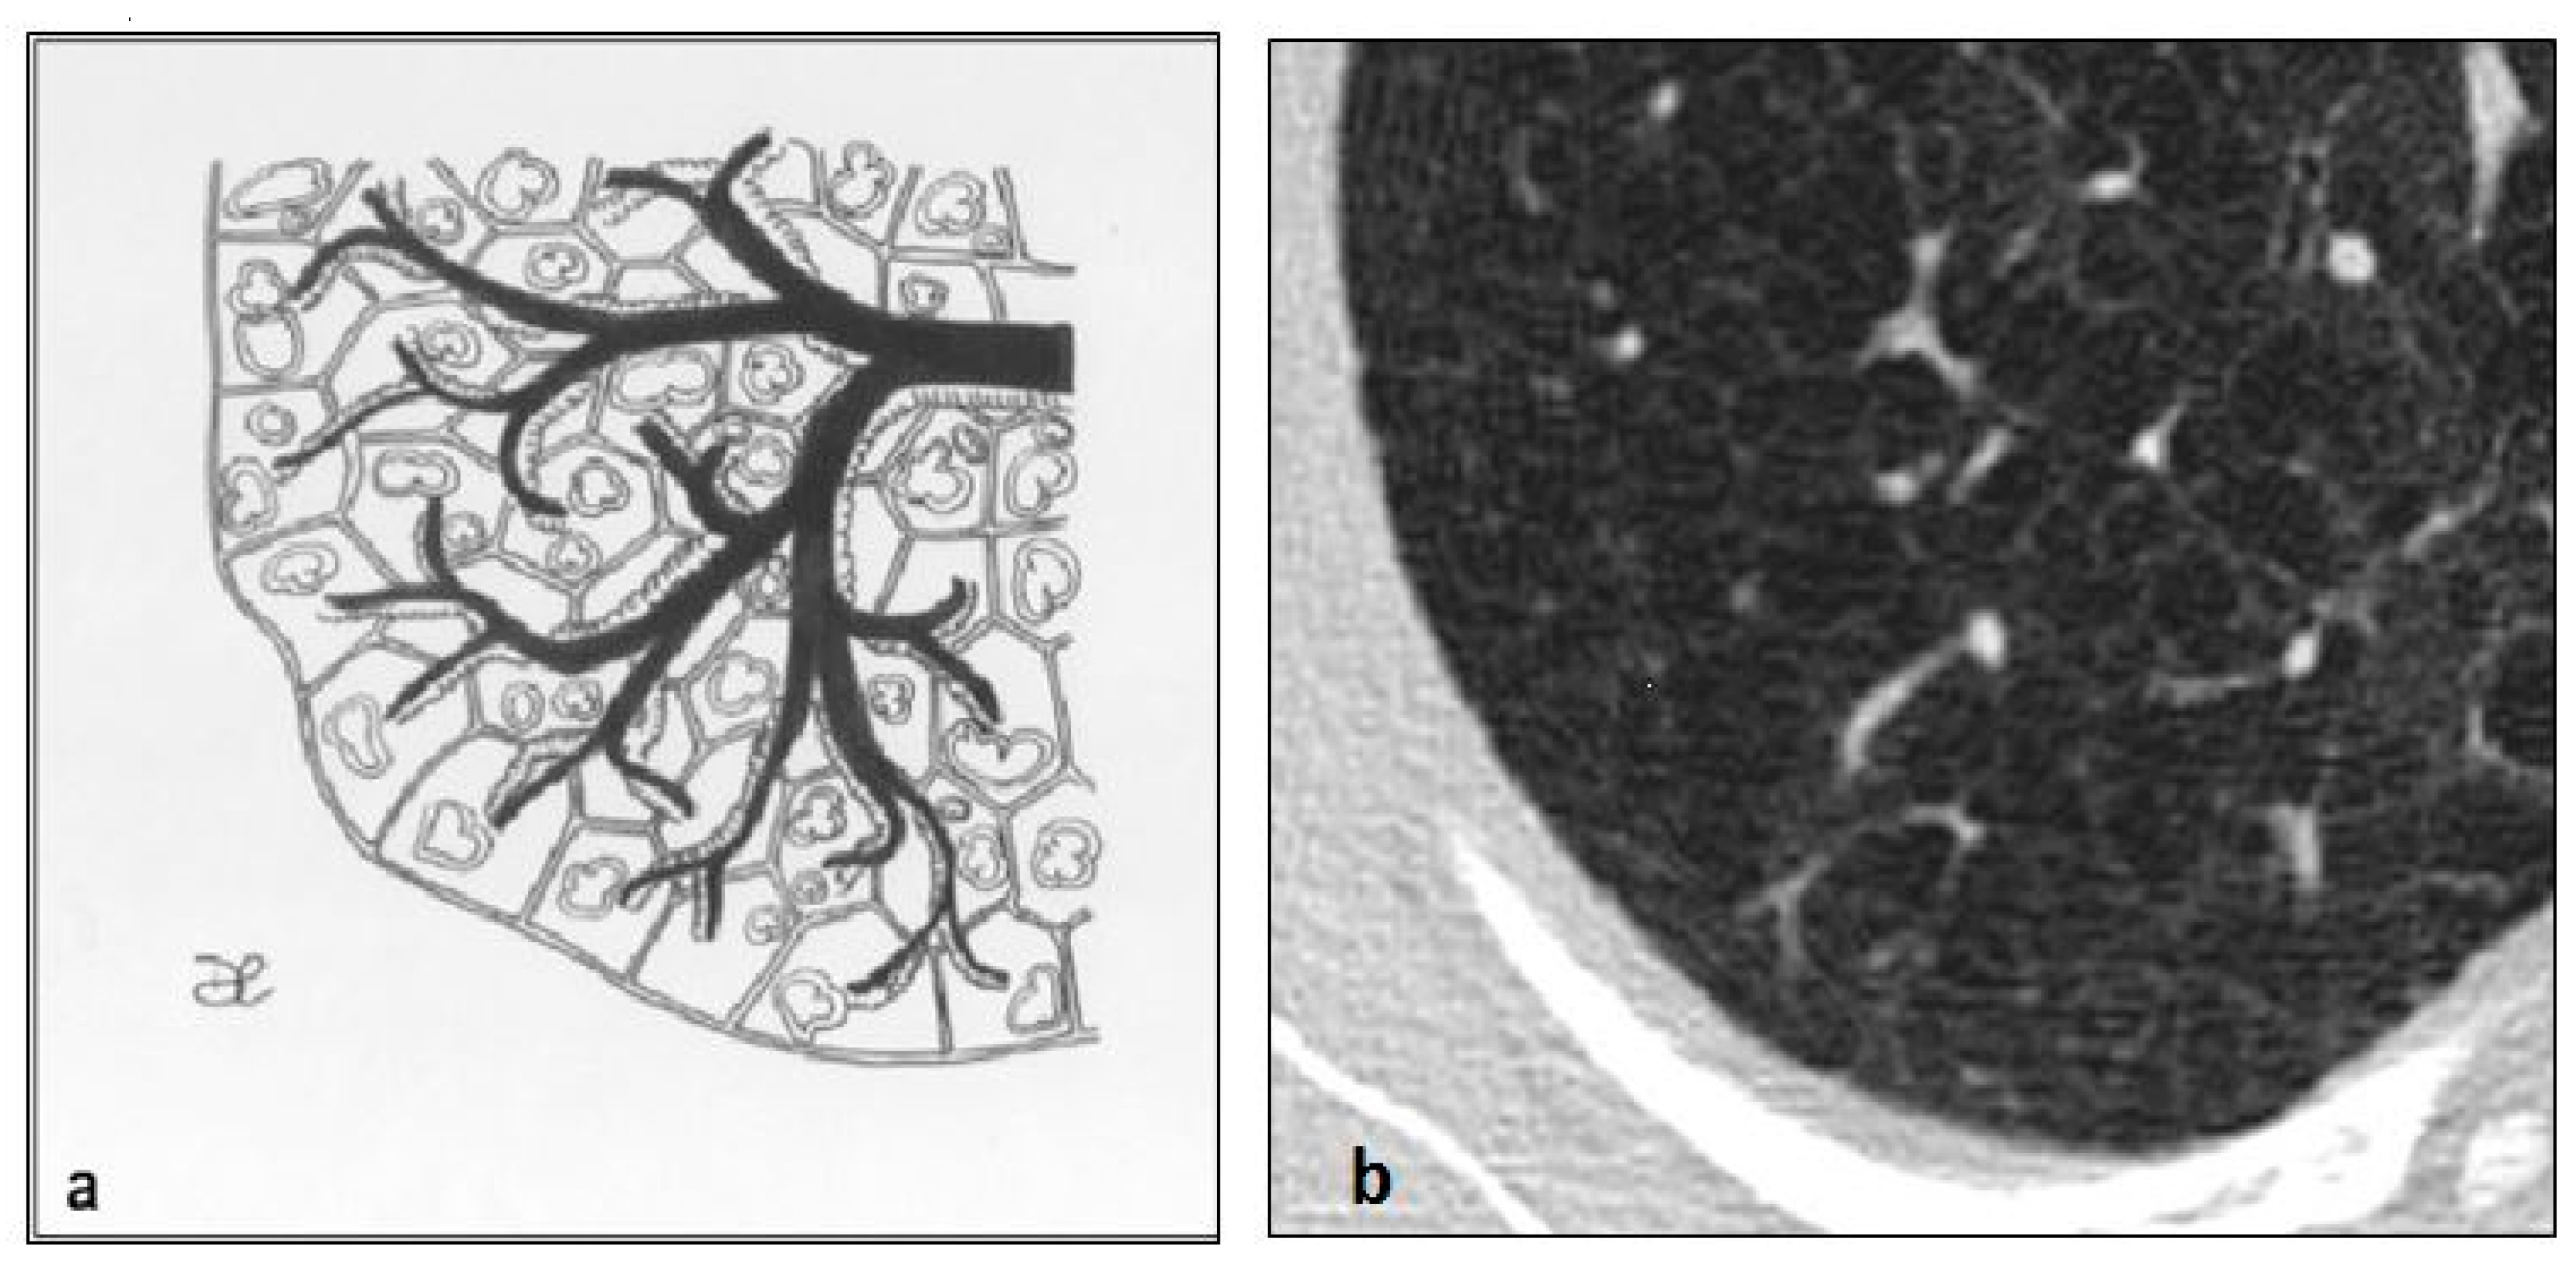

Figure 19. Aging lung manifests with the progressive air space enlargement. These cysts are thin-walled, and have a wide distribution. This figure has been partially modified from ECR 2017/C-2141 Cystic pattern in lung diseases: a simplified HRCT guide based on free-hand drawings, DC Caltabiano, V. Costanzo, L. Mammino, V. Vindigni, S. Torrisi, R. Rosso, LA Mauro, C. Vancheri, S. Palmucci.

Figure 20. Aging lung cysts pattern (a,b). These cysts can be found in any portion of the lungs; they usually show rounded shape and they are limited by thin walls. This figure has been partially modified from ECR 2017/C-2141 Cystic pattern in lung diseases: a simplified HRCT guide based on free-hand drawings, DC Caltabiano, V. Costanzo, L. Mammino, V. Vindigni, S. Torrisi, R. Rosso, LA Mauro, C. Vancheri, S. Palmucci.

The elderly lung is characterized by the progressive air space enlargement. Various studies have demonstrated a high prevalence of thin-walled cysts in many elderly individuals (25% in 75-year-old patients, absent in patients under 55 years old) [63] (Figure 19 and Figure 20); these cysts have a wide distribution and they do not show any correlation with cigarette smoking.